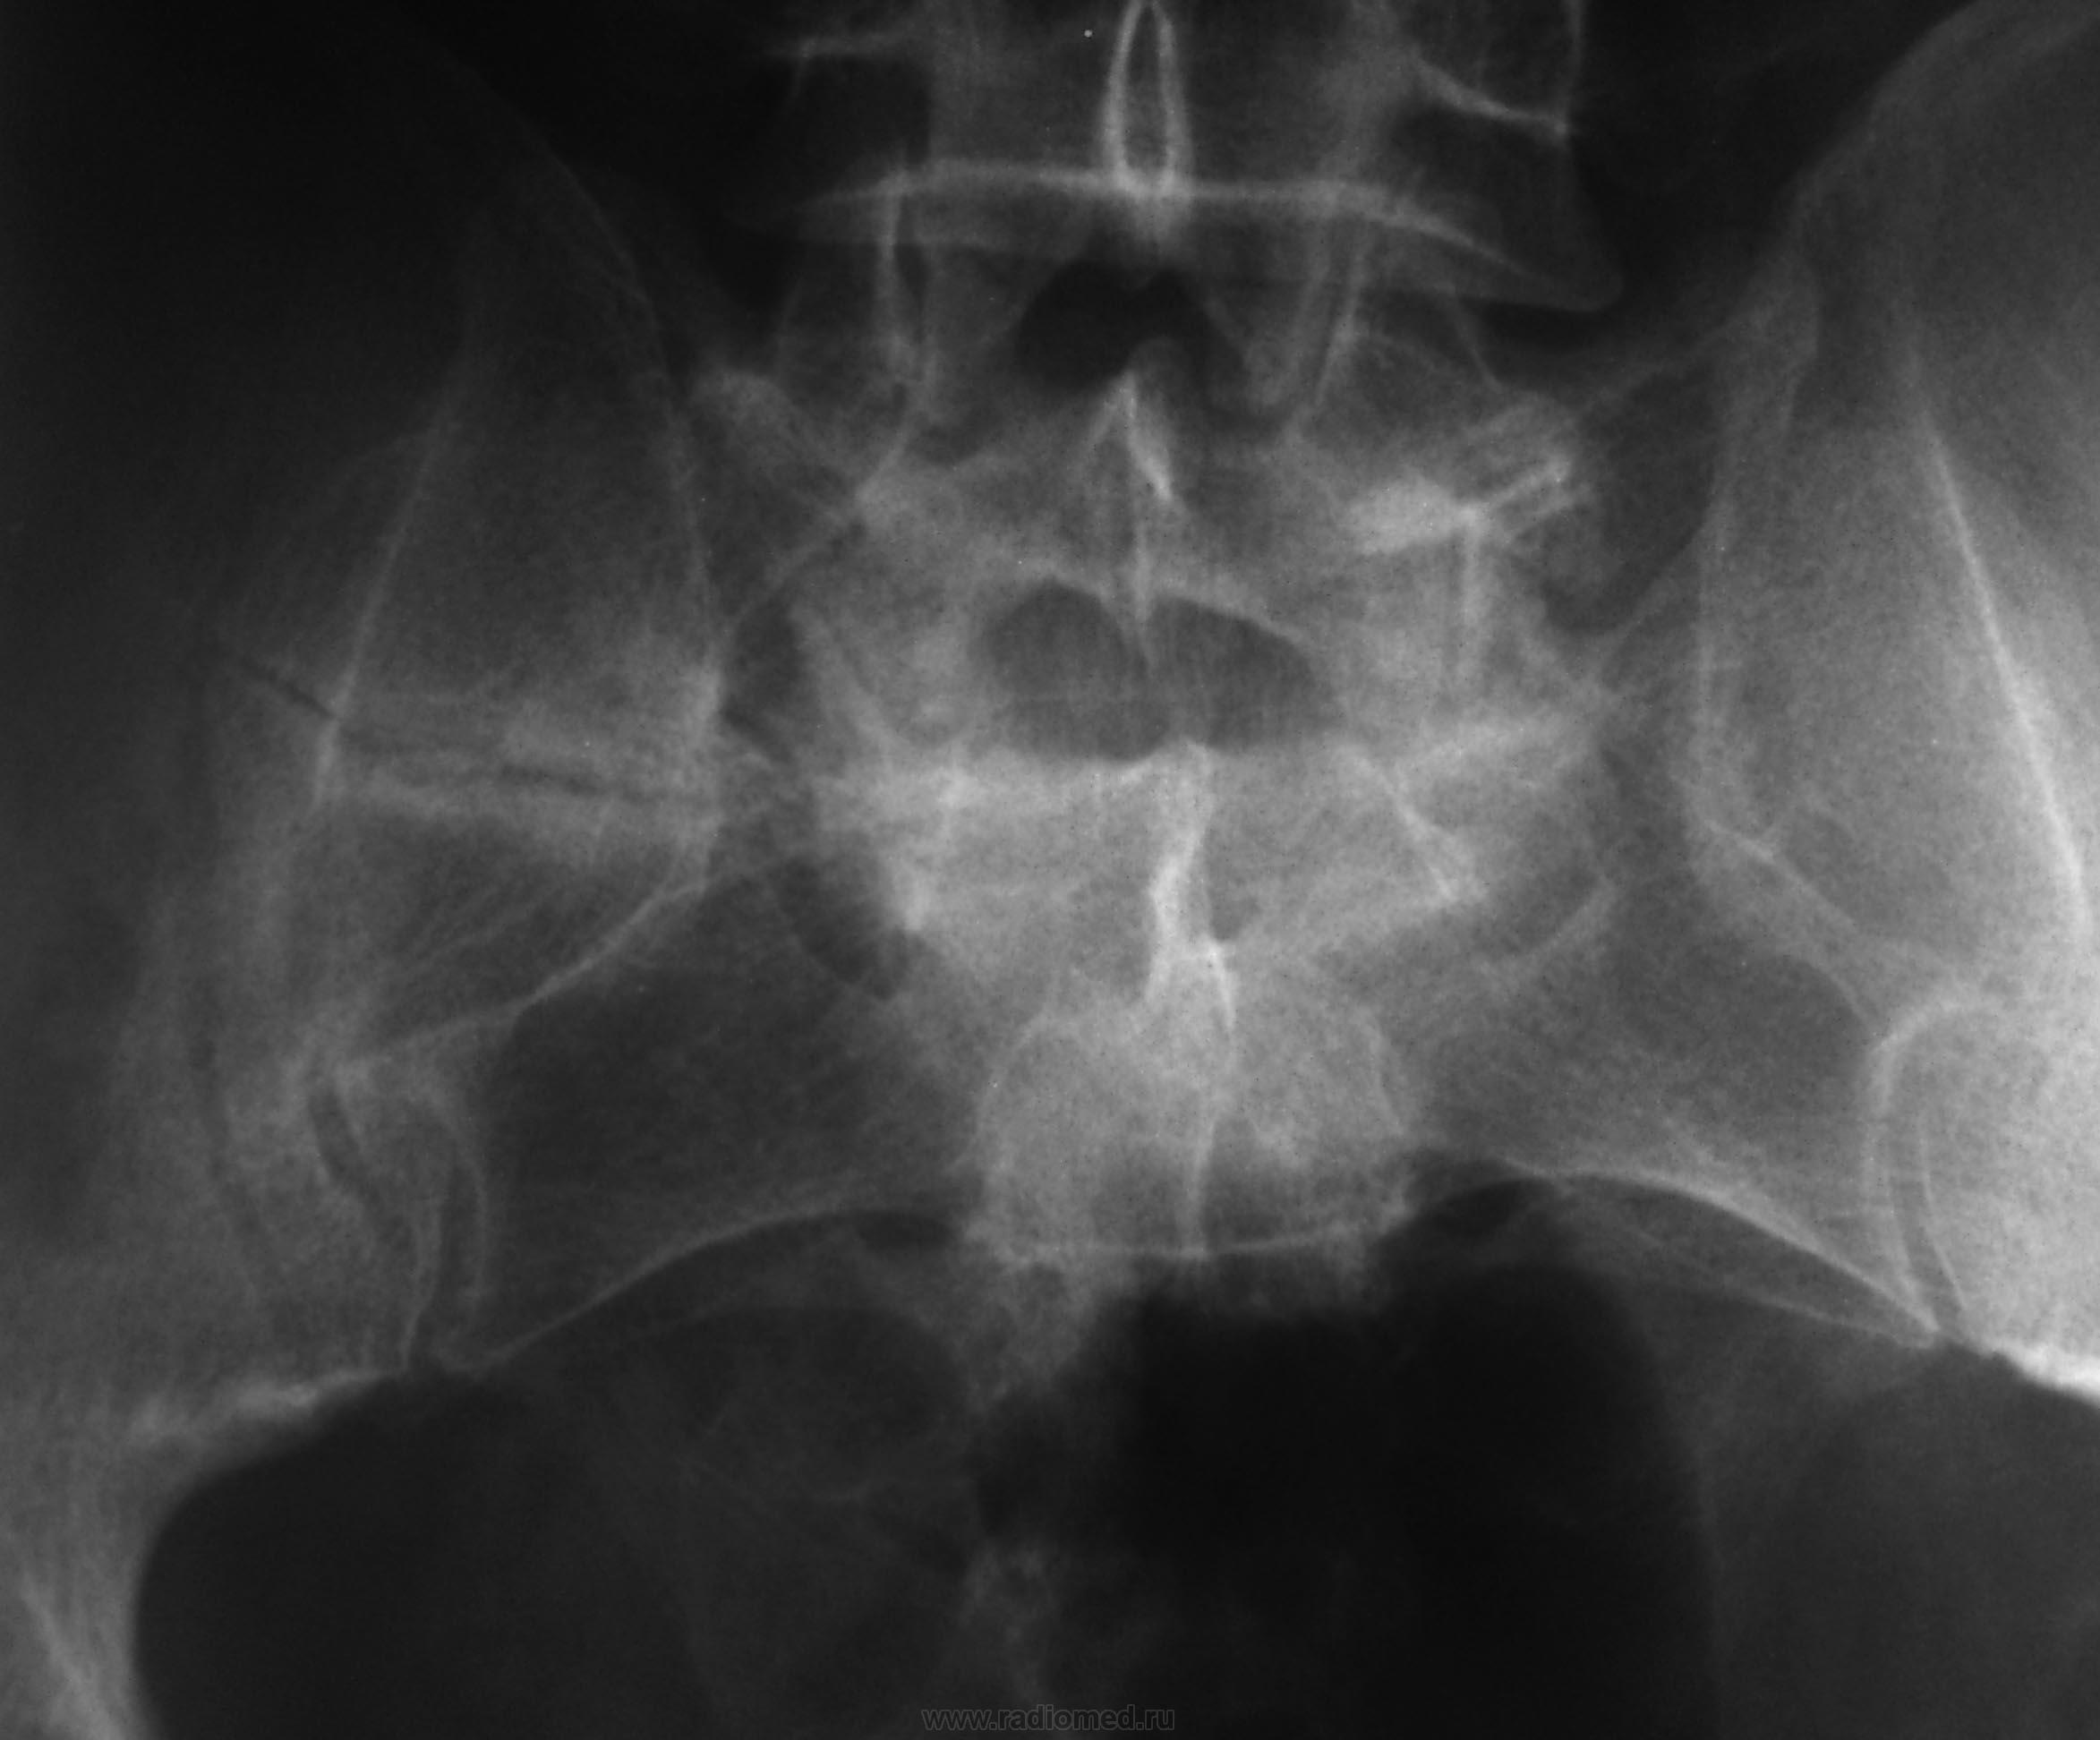

Мужчина с 1971 года рождения, очень давно попал в ДТП... Что с крестцом, неоартроз?

Да, неоартроз. Позвонки бы еще получше посчитать. Сколько их, поясничных?

Поперечная линия (на прямой рентгенограмме) справа конечно видна, но создается впечатление, что "несвежак"....

В ветке задан вопрос по поводу крестца..., и где тойный крестец? Крестец так не "рентгенографируют".

От крестца, особенно на боковой, сомнительный огрызок...

Вот симбиоз Л5 с крестцом мне не понятен, плохо проработана боковая, косвенно похоже на антелистез, но "зуб" не дам...

Рентгенограмму делали на поясничный отдел, так как задача стояла в исключении перелома L3, изменения в крестце случайная находка.

А "сплюснут" Л2....?

Компрессионный перелом L3....нет, всё ж L2

Компрессионная деформация L2, перелом боковой массы крестца справа с исходом в неоартроз.

Переходный позвонок с признаками люмбализации (наличие диска между ним и нижележащим крестцовым позвонком, а также свободный левый поперечный отросток), и сакрализации (сильно гипертрофированный правый поперечный отросток с формированием неоартроза между ним и крестцом).

Люмбализация 1 крестцового позвонка, соответственно- компрессионный перелом 3 поясничного позвонка.

Говорил уже много раз, повторюсь, пожалуй - переходный, ассиметричный, неподвижный, с образованием неоартроза справа, пояснично-крестцовый позвонок (это для данного конкретного случая).

Чтобы "не впутывать сюда ни "люмбализацию", ни "сакрализацию", так что "третий", Андрей Юрьевич сразу об этом намекнул, а потом и сказал)))